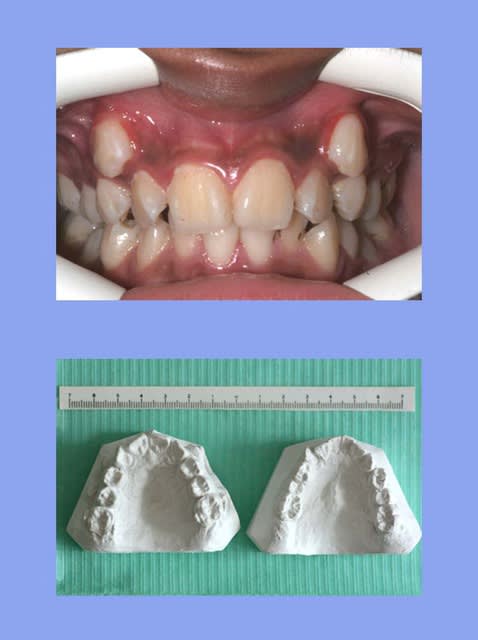

Le but des mini-vis, c'est de tout rentrer le segment antérieur ?

Risque de : perte du support labial, profil plat, constriction de l'arcade, problème ATM, apnée du someil, etc... Faut pas fermer les espaces, mais les ouvrir et retrouver les pré-molaires...bonne chance...

""Le but des mini-vis, c'est de tout rentrer le segment antérieur ?

Risque de : perte du support labial, profil plat, constriction de l'arcade, problème ATM, apnée du someil, etc... Faut pas fermer les espaces, mais les ouvrir et retrouver les pré-molaires...bonne chance...""

retrouver l'engrenement des P.M. et le reste, sans effondrement Ant.

là est tout le Pb. actuel du risque de profil plat, (sans parler du reste)

zêtes relous les mecs...bien évidemment qu'il valait mieux m'avancer la mandibule avec de la chir, chose que encore une fois je vous le répète j'ai refusé!

maintenant j'accepte les compromis...

"""bien évidemment qu'il valait mieux m'avancer la mandibule avec de la chir,"""

il n'y a pas que la chir pour avancer une Md.

@ ciwil: mouais, et il a pas vu le décalage antéro-postérieur, c'est de l'ordre de cm :-))